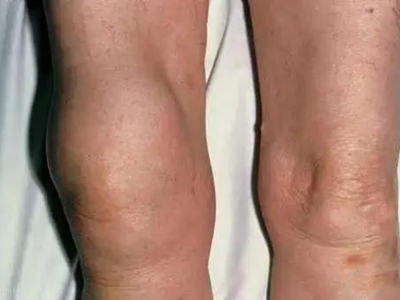

膝关节骨质增生症状图片

4、关节反复肿胀:积液多于不严重的外伤或轻度扭伤后引起关节肿胀积液,疼痛,关节周围压痛,膝关节肌肉痉挛。休息1-2个月后症状可自然消退,可以很长时间没有症状,但可因轻微外伤而反复发作,由于股四头肌无力或因疼痛,膝关节可出现“闪失”现象。

5、关节畸形:病情逐步发展,膝关节出现内翻或外翻畸形,关节骨缘增大。关节主动及被动活动范围逐步减小,关节疼痛转重,在走平路及站立时也引起疼痛感。关节韧带松弛出现关节不稳感,有些病人不能完全伸直膝关节,严重者则膝关节呈屈曲挛缩畸形。开始活动时疼痛加重,休息后缓解,以后可变为持续性疼痛。